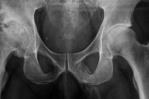

Según el estudio, estas fracturas fálicas ocurren cuando el pene erecto se dobla al golpear el “perineo o el hueso púbico con firmeza durante una actividad sexual vigorosa”, explica The New York Post.